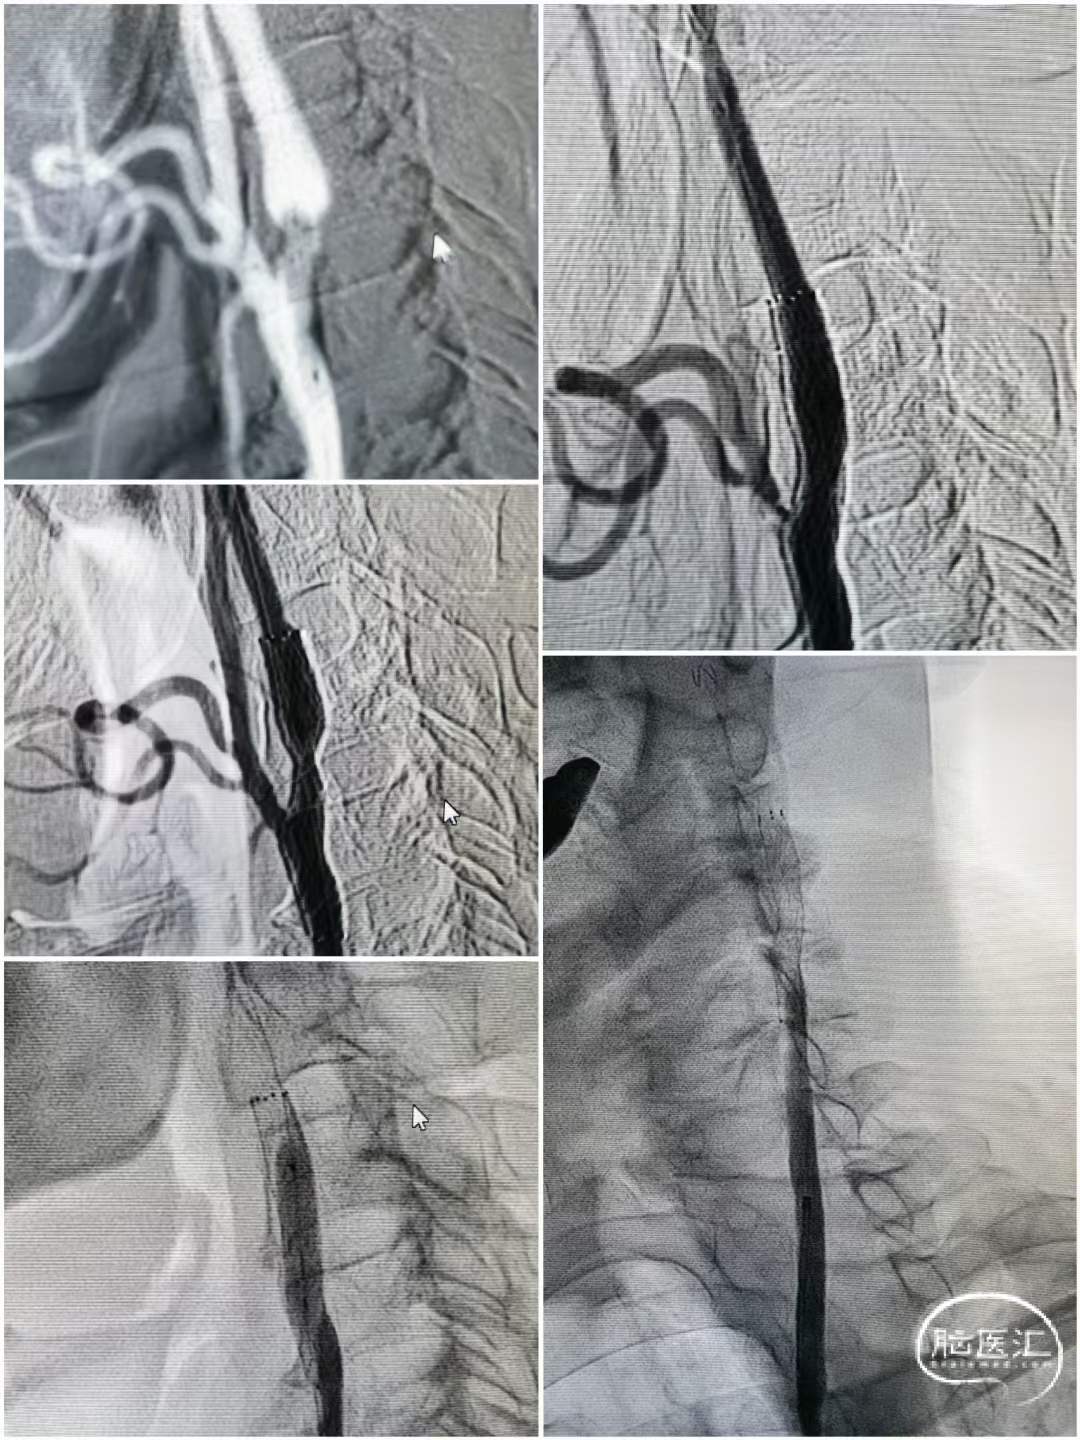

术中操作

左侧串联病变处理

跨越狭窄段释放支架,造影可见左侧狭窄明显改善。

右侧慢性闭塞处理

跨越狭窄段释放支架,造影可见右侧闭塞再通。